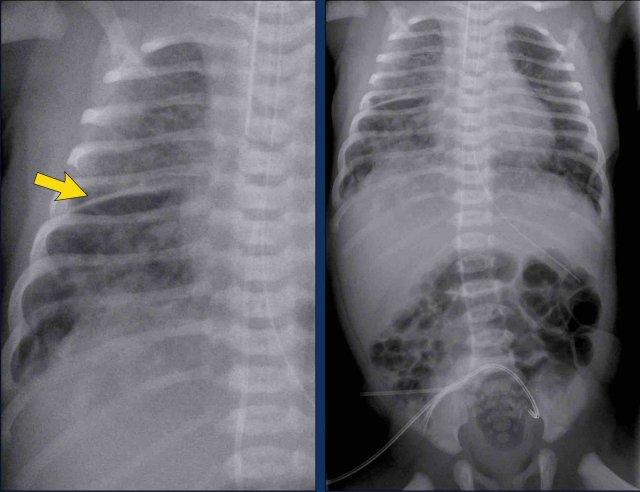

29 tuần + 1, ngày đầu tiên. CPAP.

Nhìn vào hình ảnh lần đầu.

Những phát hiện là gì?

Findings:

- Reticulogranular opacification

of lungs - Air bronchogram

- Consolidation in the right lower lobe

- Heart, vessels and

diaphragm are poorly defined. - Đặt sai vị trí catheter tĩnh mạch rốn (mũi tên), có thể nằm trong tĩnh mạch phổi.

- Nasogastric tube (NG tube) in good position.

Đây là trường hợp nặng của hội chứng suy hô hấp (RDS).

Chẩn đoán phân biệt bao gồm nhiễm trùng phổi do tình trạng đông đặc không đối xứng.